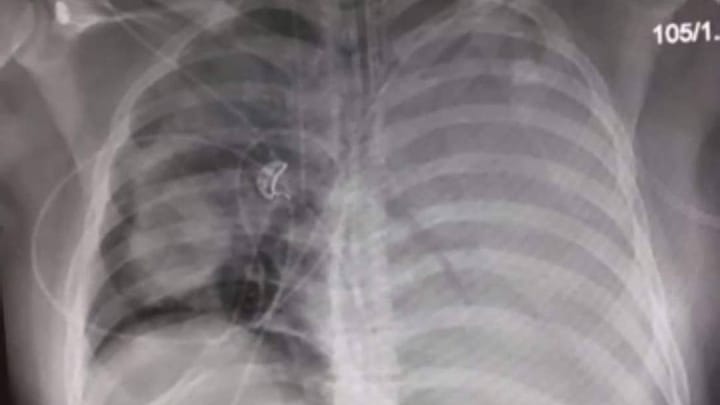

I got hit by a bacteria - My story of Legionnaires disease

WARNING: Some of the images contained in this post may be disturbing for some. I have been contemplating writing this blog now for awhile as I was unsure if I should, but after seeing a number of stories over the past months regarding Legionnaires Disease, I decided to proceed to